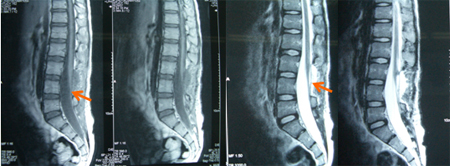

术后患者肢体疼痛缓解,未有新添的肢体功能障碍。病理结果为成熟性囊性畸胎瘤,其中可见成熟的节细胞和外周神经细胞。

术后图片示:肿瘤完全切除,圆锥和马尾清晰可见。